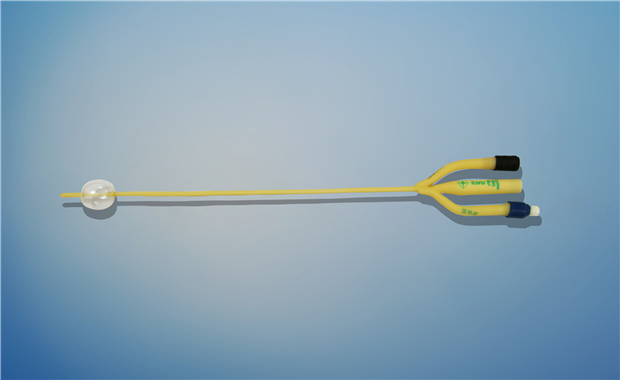

【產品名稱】一次性使用無菌導尿管(取樣型導尿管雙腔兒童型) 【型號】雙腔氣囊取樣型 【規格】:8FR-10FR 【主要結構���、性能】由膠乳為主要原材料制成,可配卡片�。

型號:雙腔氣囊兒童用規格:雙腔氣囊兒童用:8Fr(3mL)���、10Fr(3-5mL)�;結構及組成/主要組成成分:產品由導尿管����、水潤滑包(選配)組成���。雙腔由球囊腔充起錐形接口、排液腔錐形接口����、閥門、管身����、球囊、排液孔組成(尖端有普通尖頭和彎頭區分)����。水潤滑包由無菌水和水刺紗布組成,為輻照滅菌�。導尿管采用天然乳膠和親水潤滑涂...